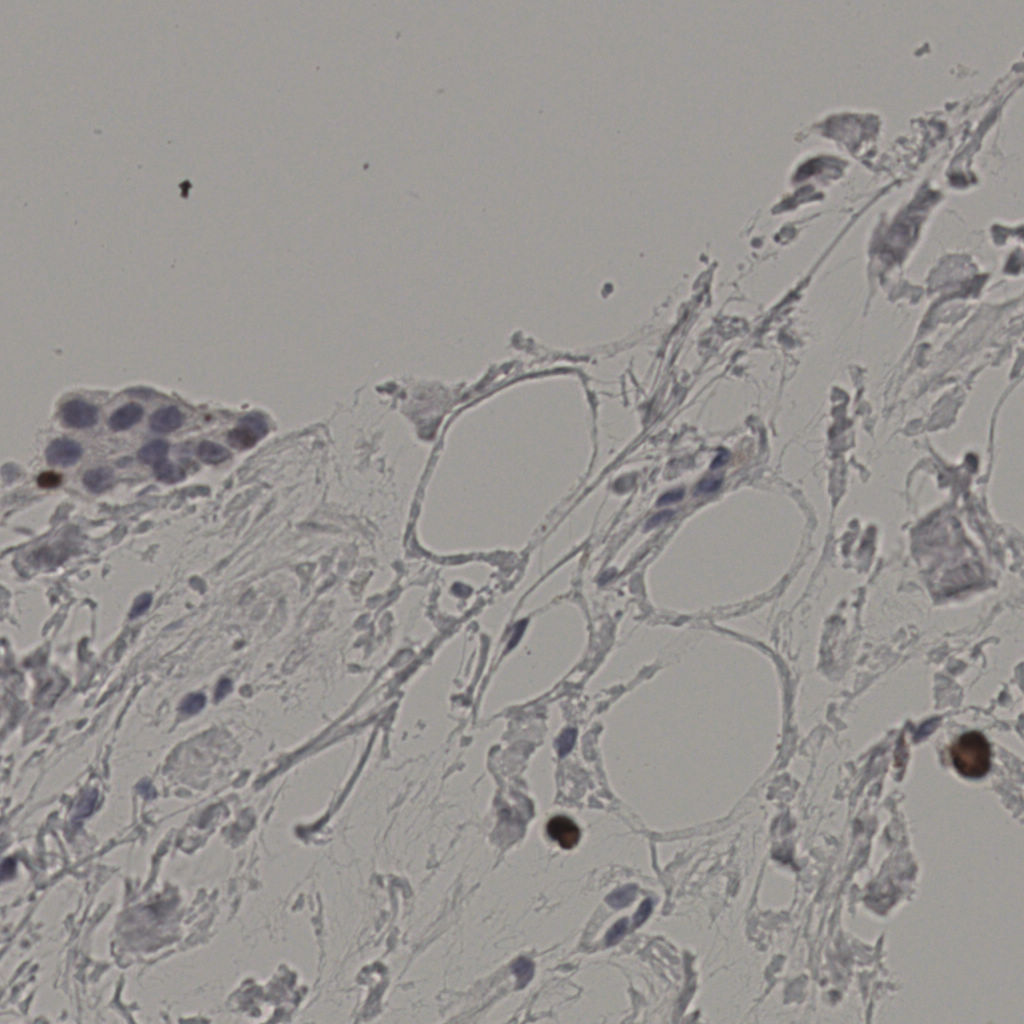

5.31%

Ki67 指数

阴 19502

阳 1093

标记后

标记前